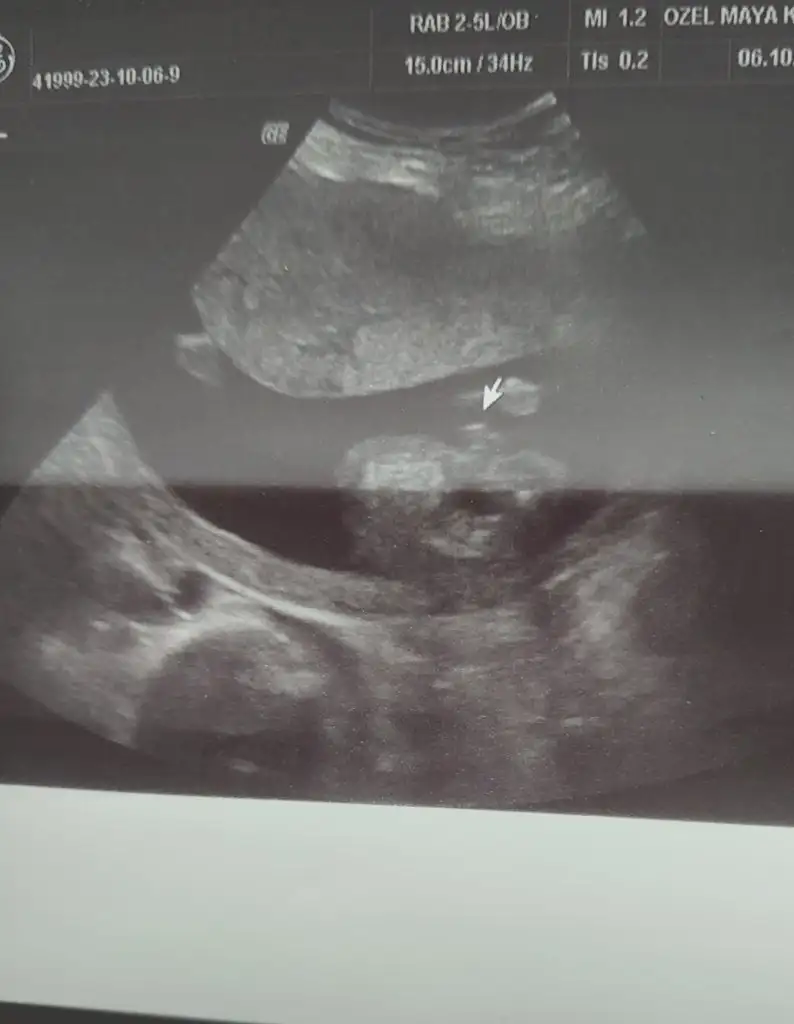

Sağlıkla gelsinBugün ki ultrason fotoğrafı

Kiz dedi doktorNeymiş cinsiyeti kuzunun